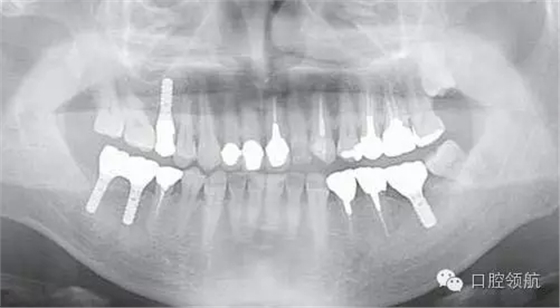

患者,38歲,男性,作為需要全面治療的患者來院?;局委熀?,右下頜磨牙區(qū)及右上頜磨牙區(qū),還有拔牙后的左下頜磨牙缺損區(qū),擬進行種植修復。圖1為初診時的曲面斷層影像,問診,模型診斷,曲面斷層檢查均未見異常,因此,最先在右下頜磨牙缺損區(qū),繼而在右上頜磨牙缺損區(qū)植入種植體,這些種植體愈合良好。

圖1 初診時的曲面斷層影像。